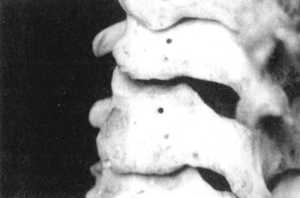

Рис. 2.15.2. Вытяжение с наклоном головы

вперед. Левый сустав. Вид сбоку |